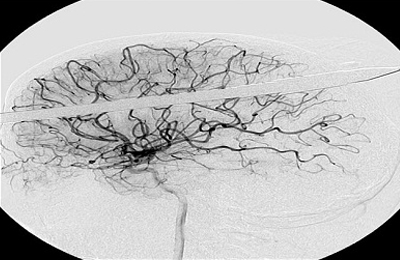

Η βέργα «χτύπησε» το Yasser μερικά εκατοστά πάνω από το δεξί του μάτι, καρφώθηκε στο κρανίο του και ακινητοποιήθηκε στο δεξί λοβό του εγκεφάλου του.

«Είναι θαύμα που δεν χτυπήθηκε κανένα από τα βασικά αιμοφόρα αγγεία του εγκεφάλου…» δήλωσε ο νευροχειρουργός Ross Bullock. «το πιο δύσκολο είναι να αντισταθείς στον πειρασμό να τραβήξεις αυτό το πράγμα έξω».

Οι γιατροί σταθεροποίησαν τη βέργα και απομάκρυναν κομμάτι μήκους 47 εκατοστών, πριν βγάλουν τις ακτινογραφίες. Στη συνέχεια χρειάστηκαν τρεις ώρες για να απομακρύνουν τη λόγχη από τον Υasser, ο οποίος νοσηλεύεται σε σοβαρή, αλλά σταθερή κατάσταση.